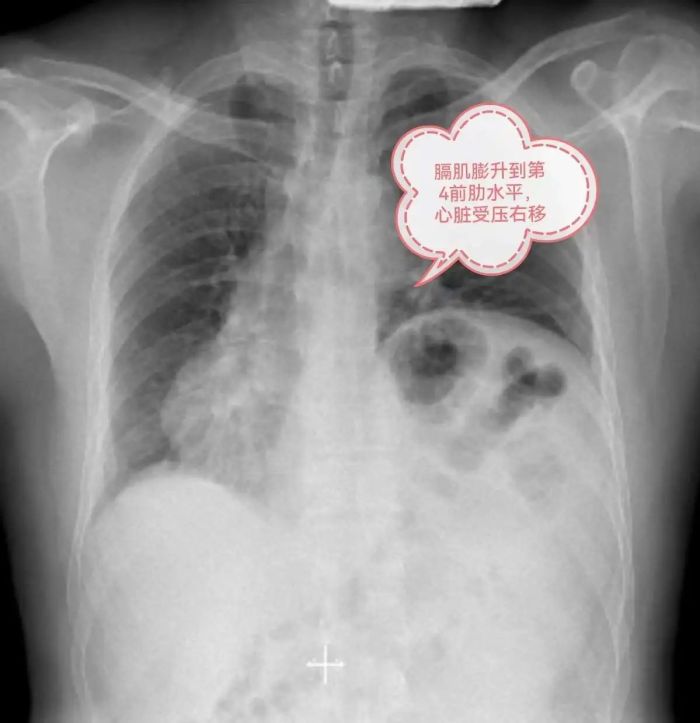

1年前,李先生症状加重,爬到2楼中途都需要缓口气休息,于是到当地某大型三甲医院就诊,入住心血管内科,做了心脏血管造影、心脏彩超、胸部CT、抽血化验等很多检查,住院两周,医生告诉他心脏没什么大问题,仅是左侧胸腹腔之间的膈肌位置有点抬高,心脏位置有些右偏,属于先天异常,无需治疗,随即李先生办理出院。

李先生来到贵州航天医院门诊,刚好遇上心胸外科陈光春主任坐诊专家门诊,陈主任听闻李先生的病情后,详细介绍了膈膨升症的相关问题,并告诉他手术后的效果,为他仔细分析病情,告诉他“心脏虽然位置有些右偏,但心功能是正常的,不会影响手术效果”。